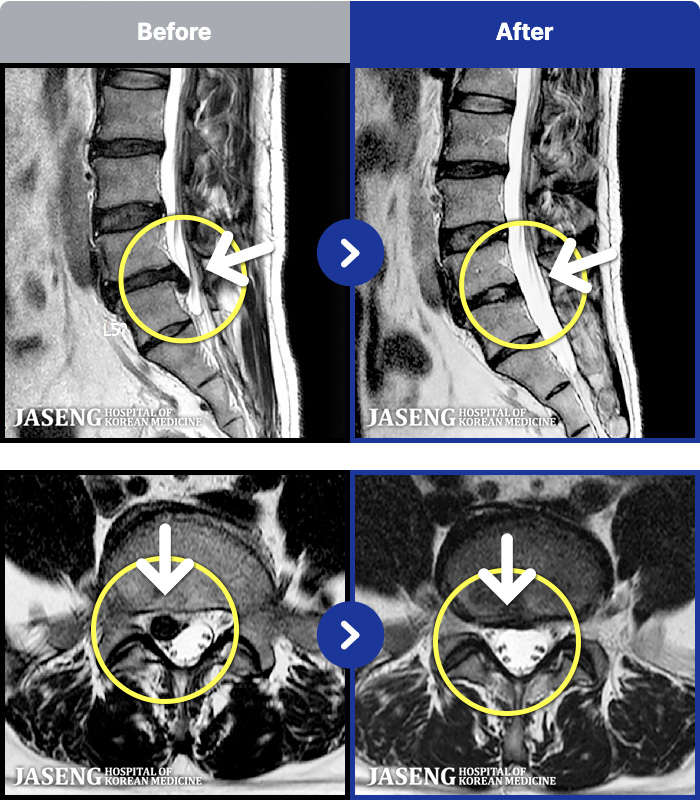

MRI ġ

1,240 MRI ũ ʸ Ȯϼ.